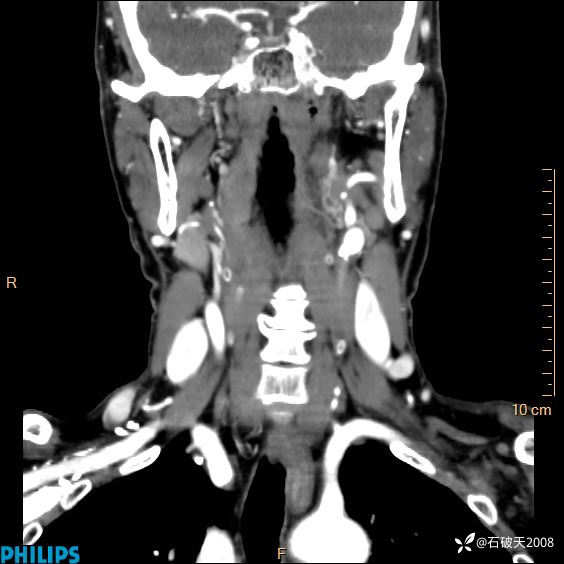

冠状位